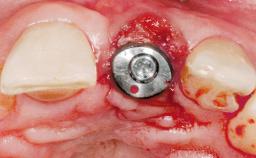

Bone Augmentation Horizontal|Simultaneous

Augmentation Materials Autogenous chips|Membrane

Abutment Type Standard

Socket Integrity Sufficient, with intact bone walls

Bone Volume Sufficient, with intact walls